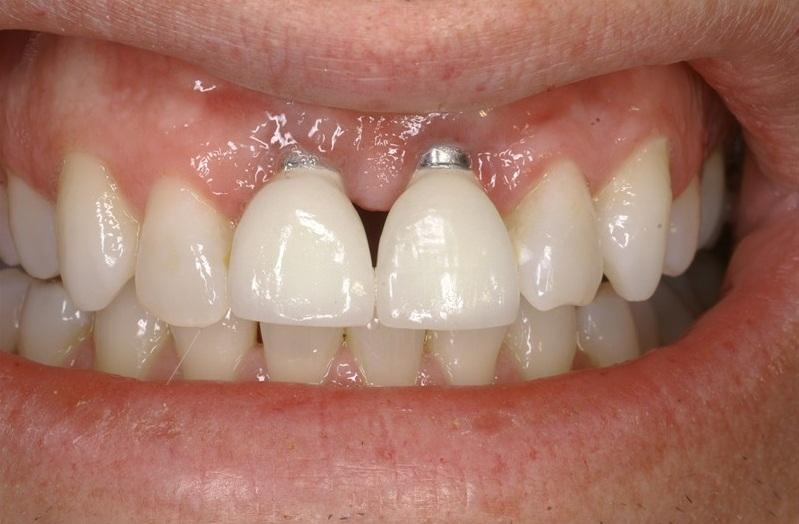

Trên thực tế, đã có nhiều trường hợp tiêu xương, tụt lợi quanh implant do kế hoạch điều trị không được xây dựng chuẩn xác ngay từ đầu.

Một trường hợp tiêu xương tụt lợi của răng implant do kế hoạch điều trị không tốt.